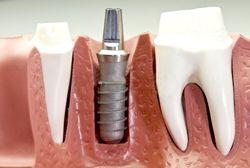

■インプラント |

||||||||

|